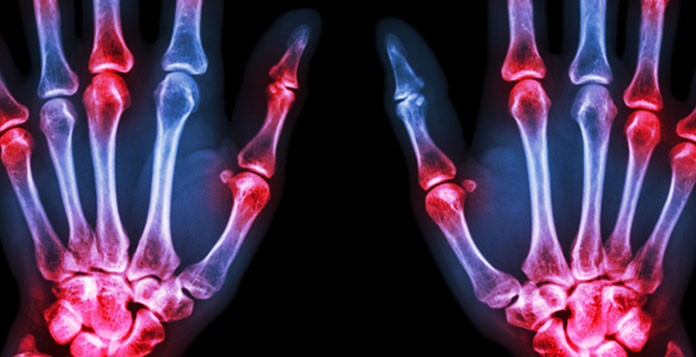

Most of you must have heard about Arthritis. This condition if you or anyone you know has it, is the inflammation or swelling of your bone joints. Pain, swelling and stiffness of your knee joint is what arthritis does to your knees.

All these three types of arthritis results in the wearing off of the cartilage in your knee resulting in the fading away of the protective space between the joints. When the space fades away, the two ends of the bone scrape against each other causing pain in the knee. Immense pain.